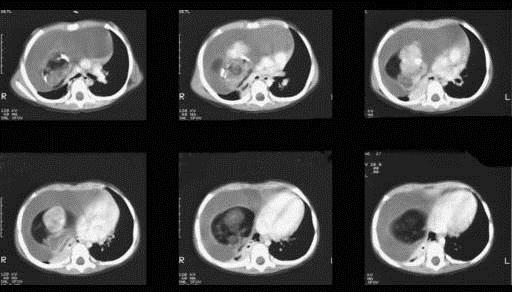

问题 12岁,女,咳嗽、咯血1个月,咳出毛发、钙化物,请结合图片,选择最可能的诊断 ( )

选项 A.肺间质纤维化 B.肺曲菌病 C.肺结核 D.畸胎瘤 E.肺癌

答案 D